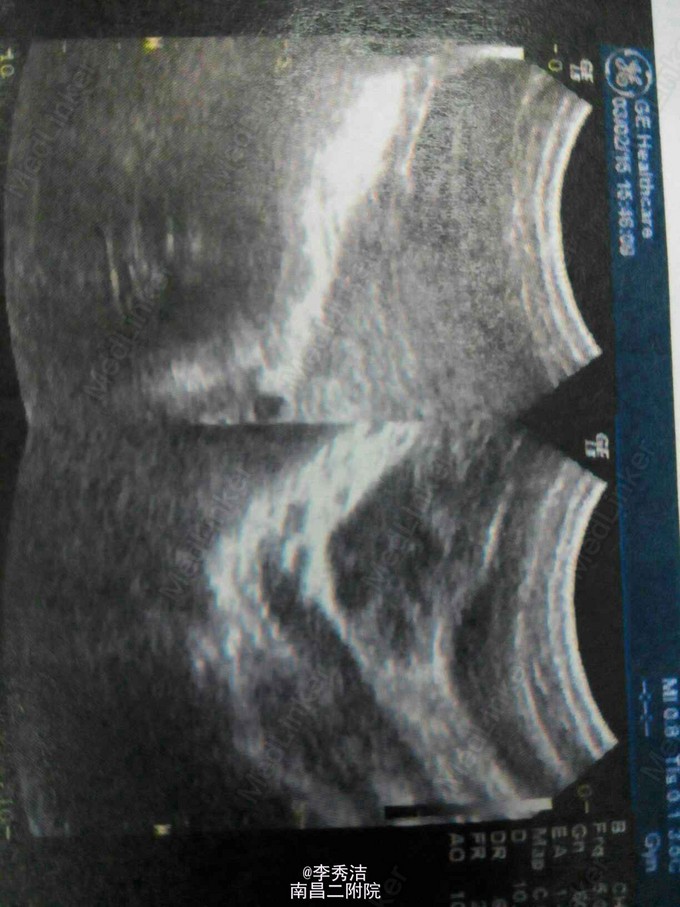

患者,女,10岁,因“反复右下腹痛4天,发现盆腔包块4天”入院,彩超检查示幼稚子宫,右侧盆腔10*10*9cm肿物,择日腹腔镜手术,术中见右侧卵巢肿瘤大小约10*10*9cm肿物,表面见一长约3cm破裂口,囊内液黄色烂肉状。术中冰冻切片示卵巢囊瘤。